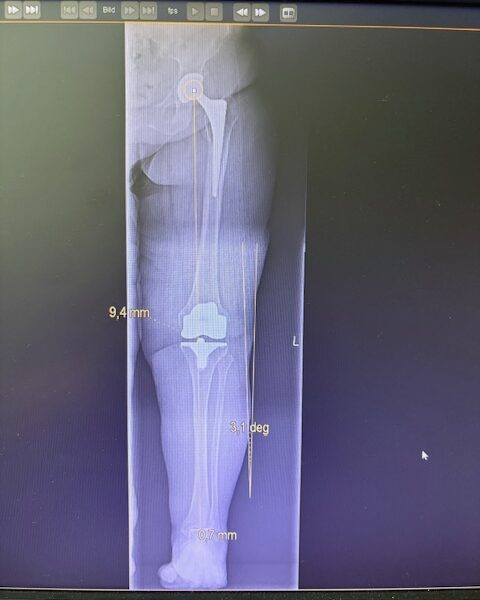

Ο προεγχειρητικός ψηφιακός σχεδιασμός

Πραγματοποιήθηκε σε ειδική ακτινογραφία ολόκληρων των δύο κάτω άκρων. Σε αυτό το ψηφιακό μοντέλο σχεδιάστηκε με ακρίβεια το είδος, το μέγεθος και η ακριβής θέση των προθέσεων, με βάση τα ανατομικά χαρακτηριστικά της ασθενούς.

Ο ψηφιακός σχεδιασμός επιτρέπει απόλυτη εφαρμογή των μοσχευμάτων, ελαχιστοποιώντας τα περιθώρια απόκλισης και εξασφαλίζοντας άριστη ευθυγράμμιση και κινηματική ισορροπία του γόνατος.